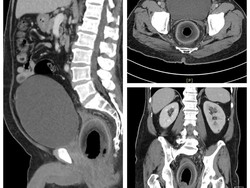

Rumah Sakit dr Saiful Anwar (RSSA) menjadi pusat rujukan penanganan striktur uretra. Striktur uretra merupakan kondisi penyempitan saluran kencing.